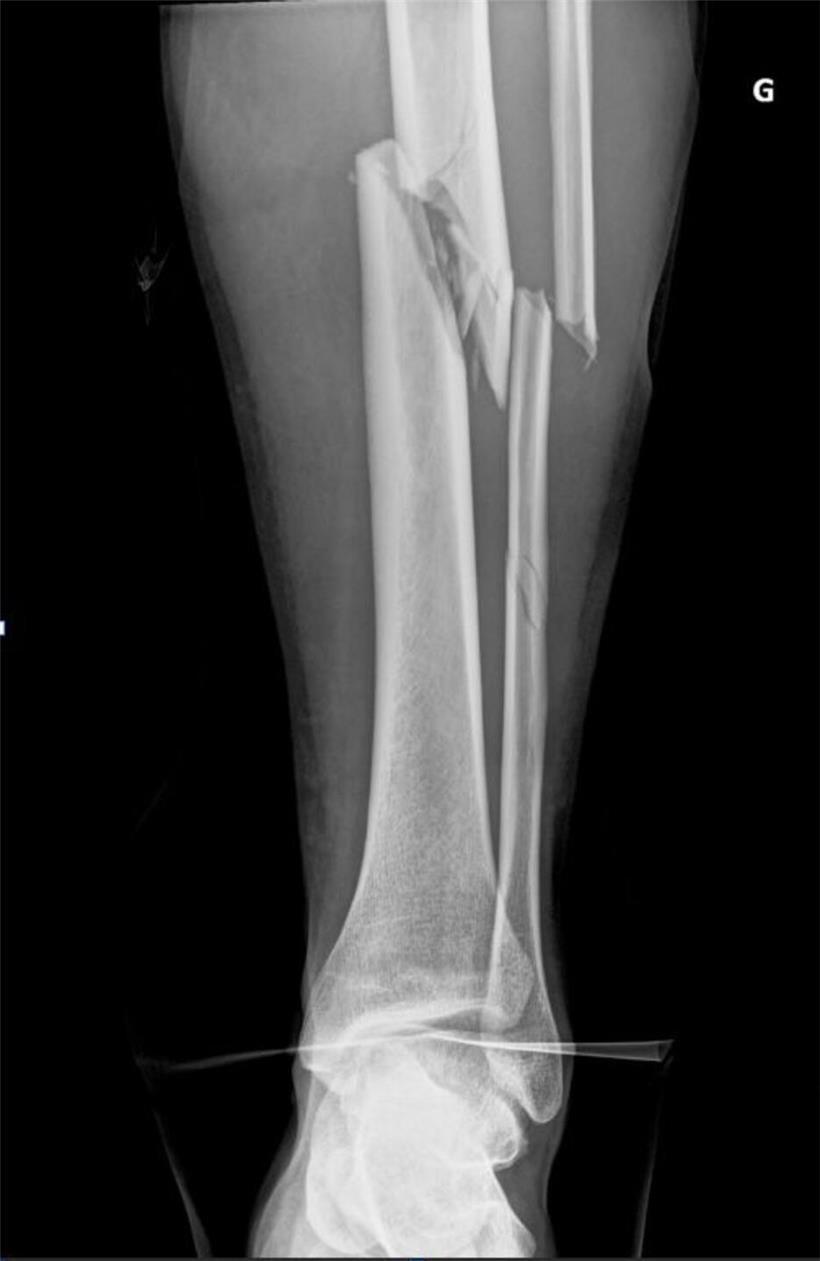

Im Krankenhaus stellten die Ärzte Brüche von Schien- und Wadenbein sowie einen Bruch des Oberschenkelknochens knapp oberhalb des Knies fest. Noch am selben Tag wurde Henx operiert. Ein 37 Zentimeter langer Nagel stabilisiert seither sein Unterbein.

Röntgenbild von Schienbein- und Wadenbeinbruch bei Unfall mit sichtbarem Knochenbruch und Frakturstellen

Die Röntgenaufnahmen zeigen den Bruch des Schien- und Wadenbeins Foto: Privat